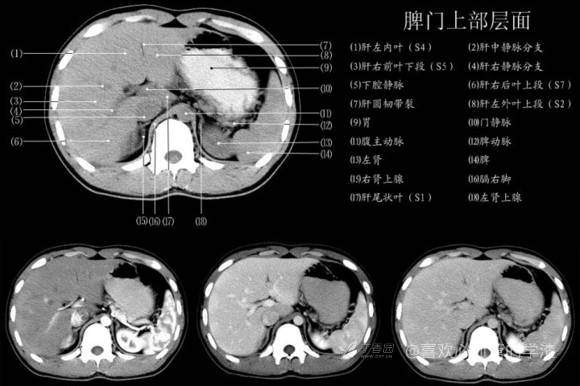

其实你离掌握上腹部 CT 影像只有一套高清实用图谱的距离,下面把我最喜欢的这本图谱分享给大家,为了方便阅读,我加了中文标识。后面附赠几张血管相对位置解剖关系图片,帮助大家理解(文中多图,建议在 wifi 环境下查看)。